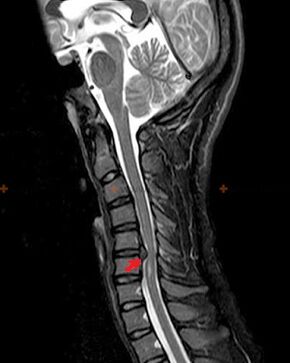

Diagnose und radiologische Anzeichen.

Osteochondrose ist eine Röntgendiagnose, da ein detailliertes klinisches Bild nur zum Zeitpunkt der Exazerbation vorliegt, während Veränderungen in der Wirbelsäule bei völligem subjektivem Wohlbefinden einer Person auftreten können. Ohne Röntgenuntersuchung kann nur von einem Verdacht auf Osteochondrose gesprochen werden, da ähnliche Symptome auch durch andere Erkrankungen (Myositis, Wirbeltumoren und andere) verursacht werden können.

Zur Diagnose einer Osteochondrose werden folgende Untersuchungsmethoden eingesetzt: Radiographie (vorzugsweise mit Funktionstests), MSCT und MRT. Diese letzte Studie ist vorzuziehen, da sie uns eine sehr klare Visualisierung des Zustands der Zwischenwirbelstrukturen ermöglicht.

Zu den radiologischen Anzeichen einer Osteochondrose zählen folgende Veränderungen der Wirbelsäule:

- Reduzierte Höhe der Bandscheiben.

- Vorhandensein marginaler Knochenwucherungen.

- Verletzung der Lage der Wirbel relativ zueinander.

- Verformungen von Wirbelkörpern und Bögen usw.

Das Vorliegen der oben beschriebenen Veränderungen sowie mittels MSCT und MRT festgestellte Veränderungen in der Struktur der Bandscheibe dienen als zuverlässige Anzeichen für das Vorliegen einer Osteochondrose.